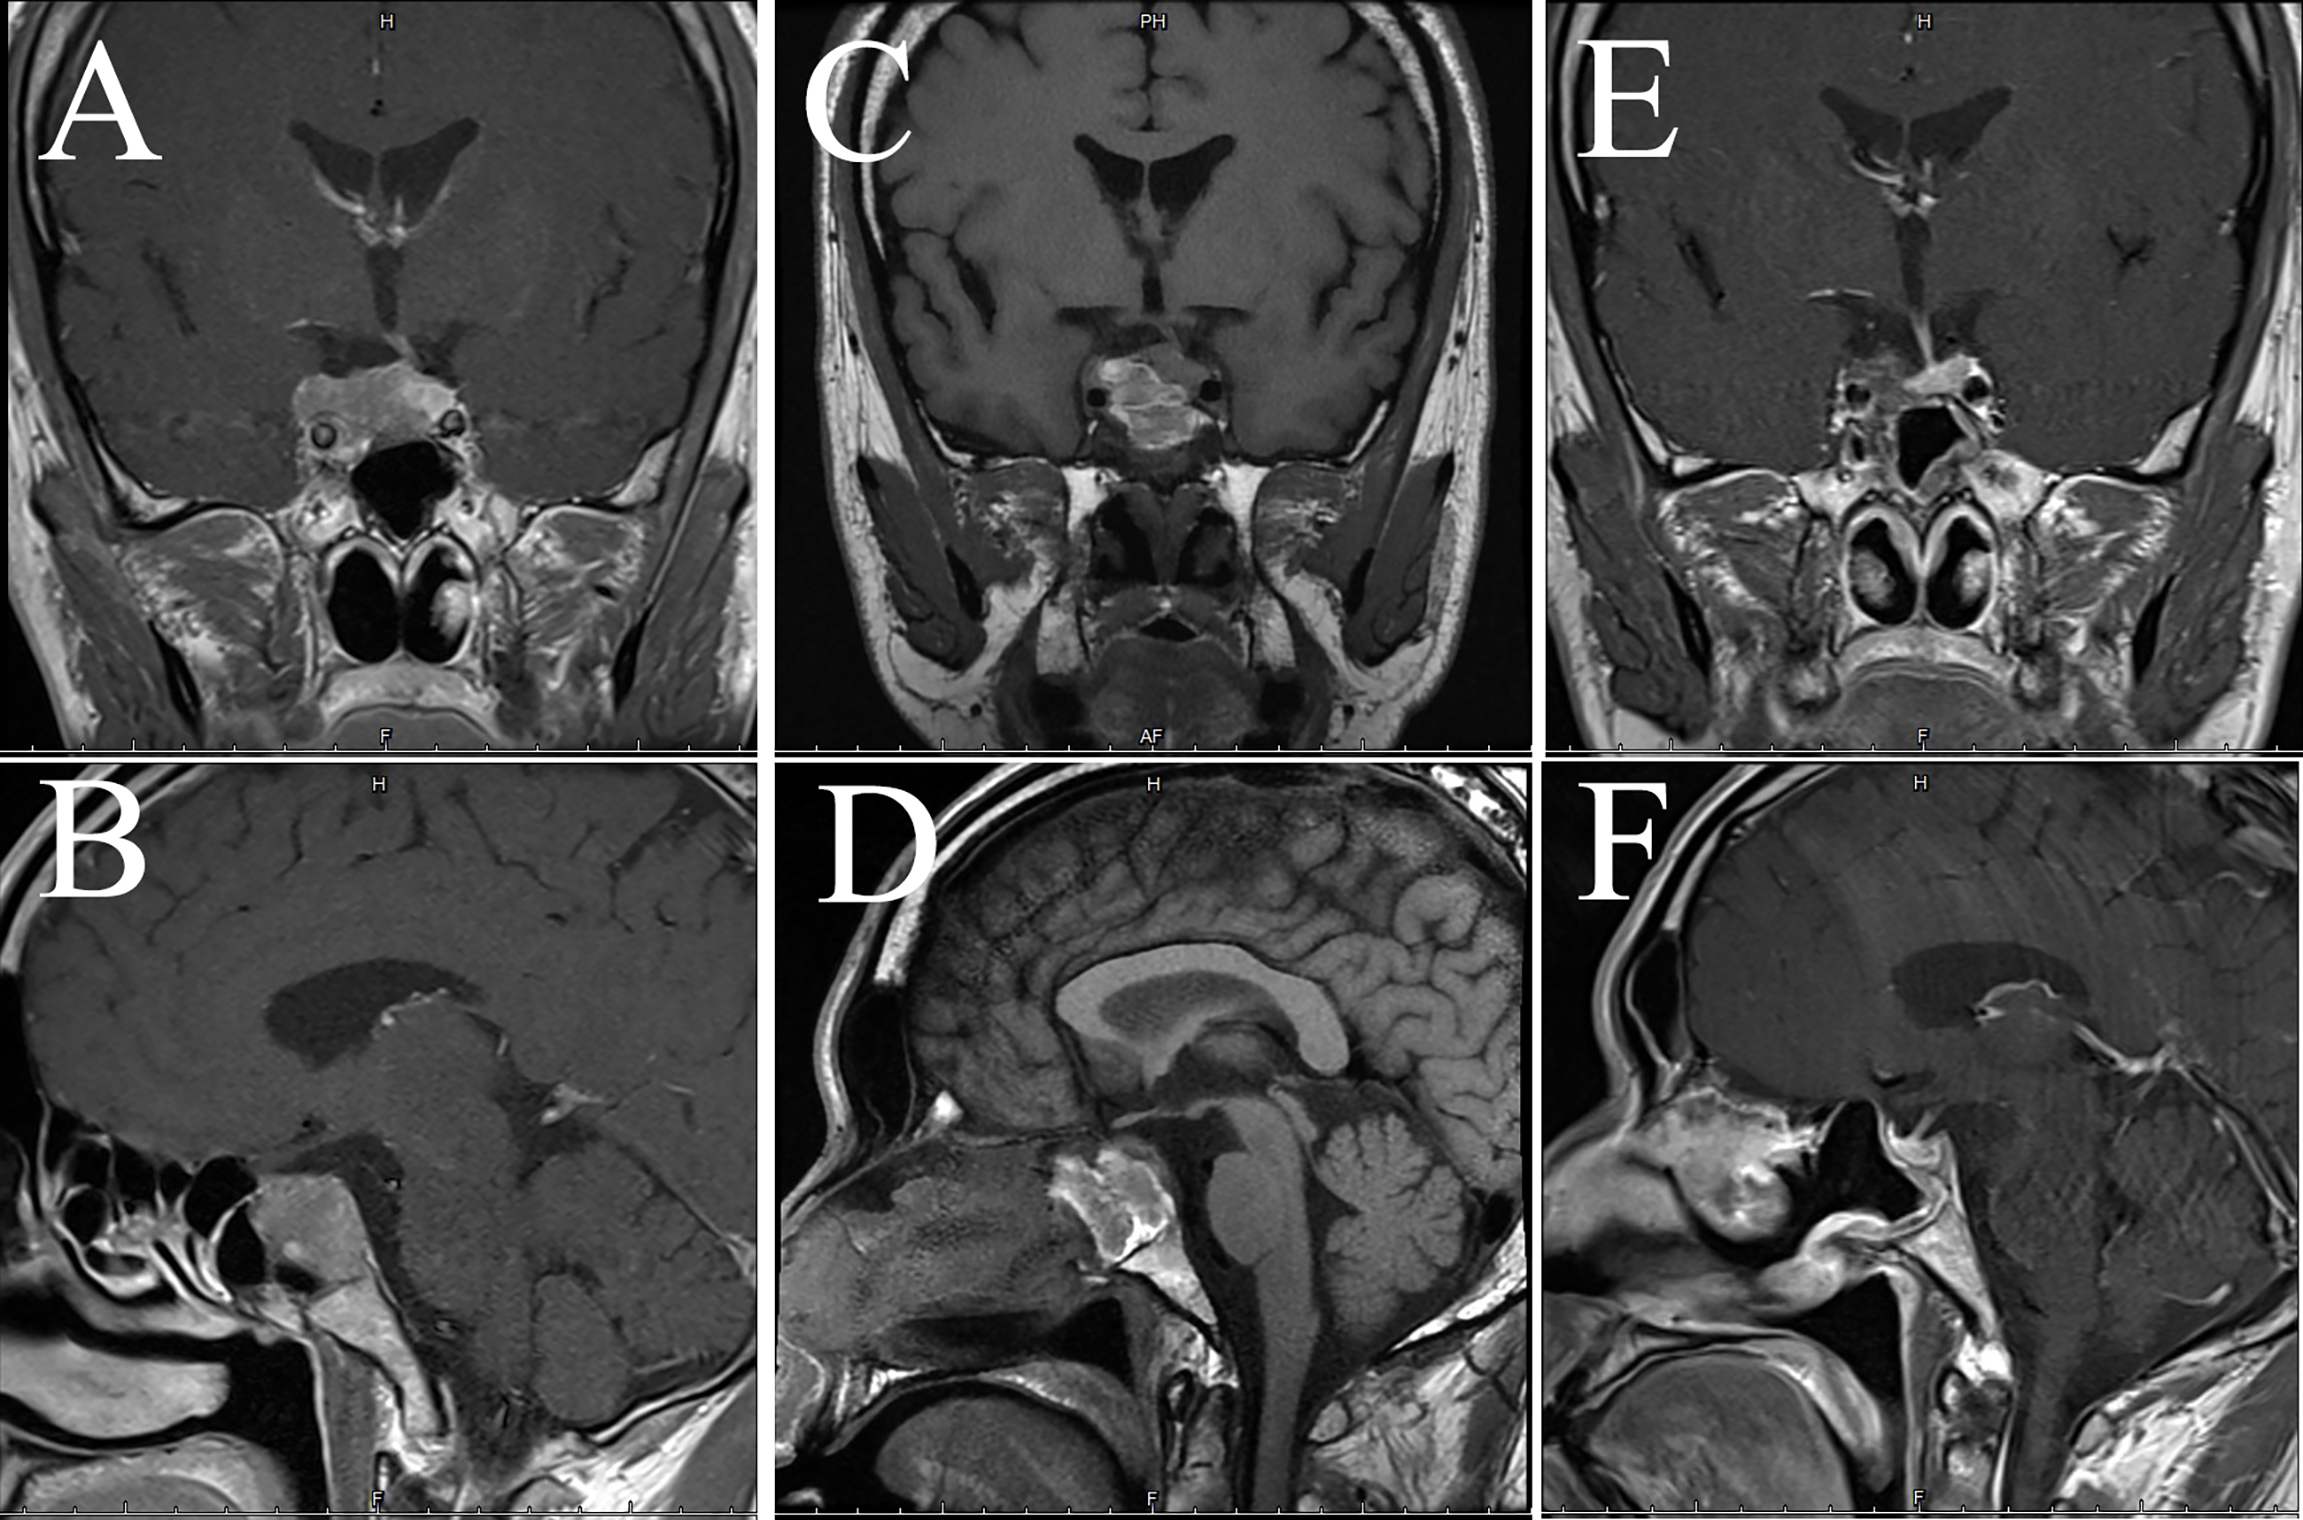

Figure 6

MRI examination of case 3. The images show coronal and sagittal MRI of the patient’s head preoperatively (A, B), one week postoperatively (C, D), and three months postoperatively (E, F), respectively.

Figure 8

Imaging examination of case 4. The images show coronal and sagittal MRI of the patient’s head preoperatively (A, B), one week postoperatively (C, D), and three months postoperatively (E, F), respectively.